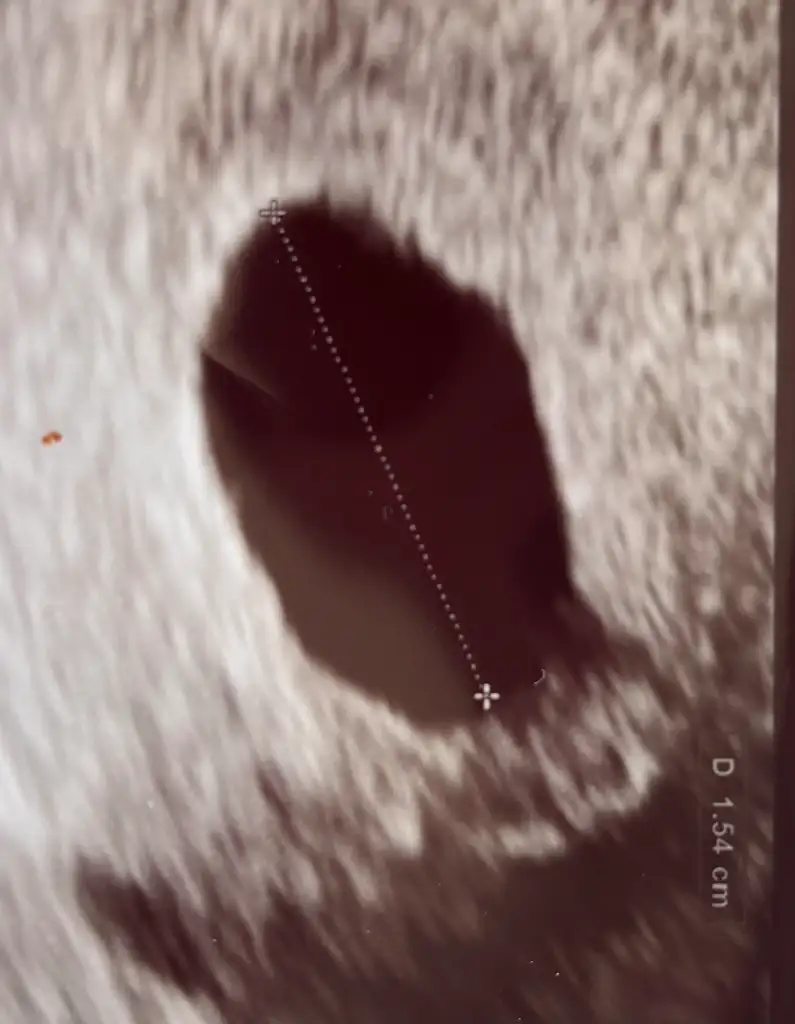

benim ultrason görüntüm bu şekilde

Eklentiler

• IMG_8376.webp